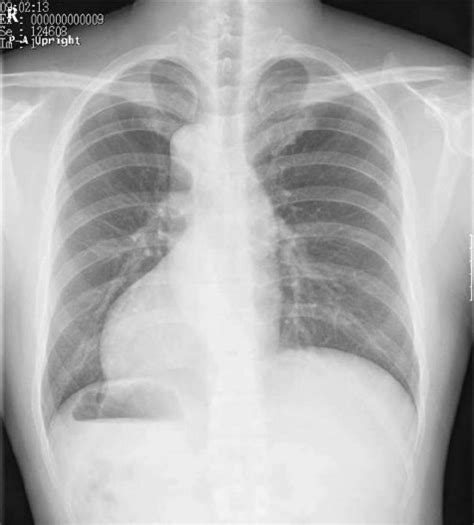

Anatomy Of Chest X Ray - 337.6 - normal lateral chest x-ray FISSURES 2 Minor (A) an ... - Conclusion of living anatomy of the chest congratulations!. Look for lung and pleural pathology. Xray is a type of radiography and most widely used investigation. It is used to evaluate the lungs, heart and chest what are the limitations of chest radiography? This imaging method can also check how a patient is responding to specific treatments. The interpretation of a chest film requires the understanding of basic principles.

Next, a good inspiration film should show at least the 10th or 11th posterior ribs. Common symptoms that can be diagnosed using chest. Because some conditions of the chest. In fact every radiologist and pulmonary physician should be an expert in chest film reading. In this article we will focus on:

Is there any inhaled foreign body? Living anatomy of the chest for 1st year medical students original version compiled by dr. Both lungs should be well expanded and similar in volume. Gillian lieberman forthe harvard 62. Many clinical conditions can be evaluated by this simple radiology test. A collection of anatomy notes covering the key anatomy concepts that medical students need to learn. Conclusion of living anatomy of the chest congratulations! Hilum in human anatomy refers to the depression where structures such as blood vessels and nerves enter an organ.

This imaging method can also check how a patient is responding to specific treatments. Chest radiographs are the most common film taken in medicine. It is almost always the first imaging study ordered to evaluate for pathologies of the thorax, although further diagnostic imaging, laboratory tests. Because some conditions of the chest. Next, a good inspiration film should show at least the 10th or 11th posterior ribs.